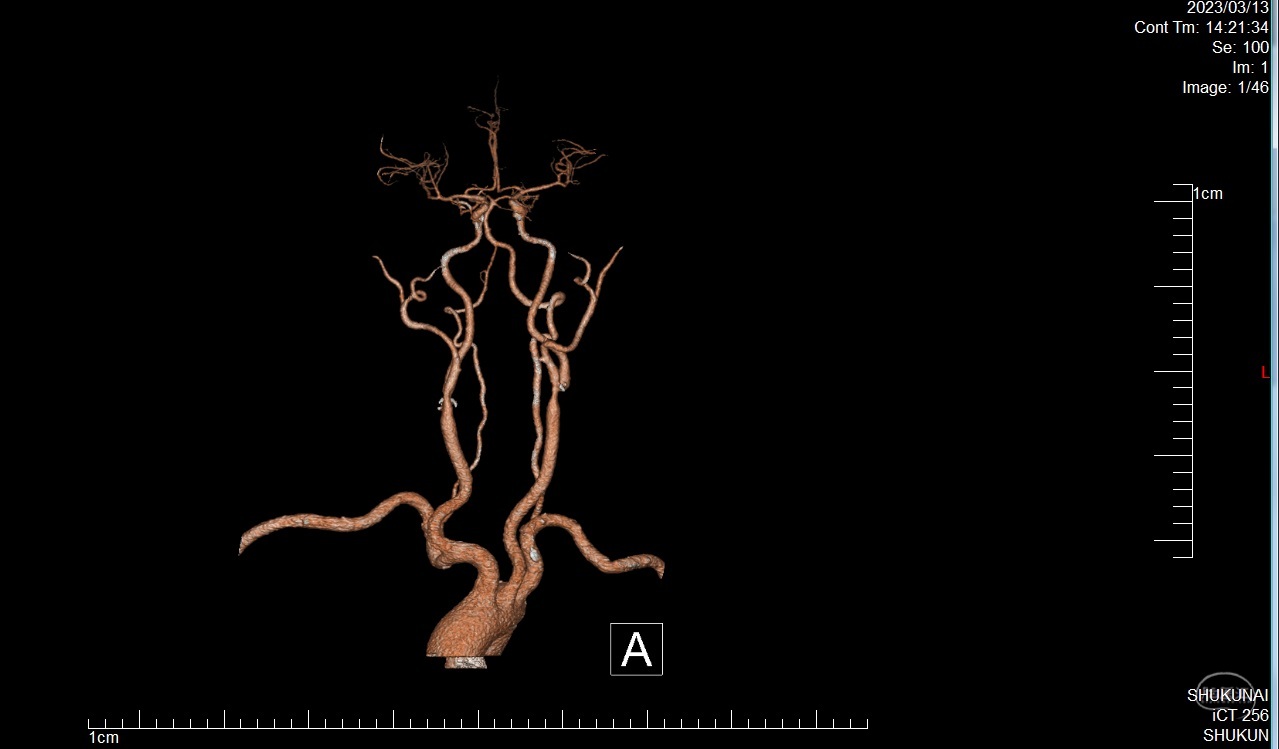

患者李XX,男性,63岁,主因右肢无力1月入院

既往高血压病史,糖尿病史,脑梗死病史5年,遗留优质活动不利,冠心病病史

查体:BP:129/75mmHg,神情,言语正确,四肢从嘱,GCS:15分,双侧瞳孔各3mm,对光反射灵敏,右侧肌力4级,左侧5级

颈动脉内膜剥脱术

患者李XX,男性,63岁,主因右肢无力1月入院

既往高血压病史,糖尿病史,脑梗死病史5年,遗留优质活动不利,冠心病病史

查体:BP:129/75mmHg,神情,言语正确,四肢从嘱,GCS:15分,双侧瞳孔各3mm,对光反射灵敏,右侧肌力4级,左侧5级